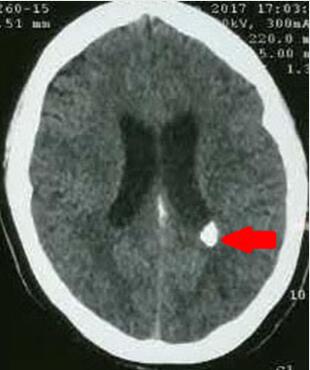

图1 1月余前脑室出血CT